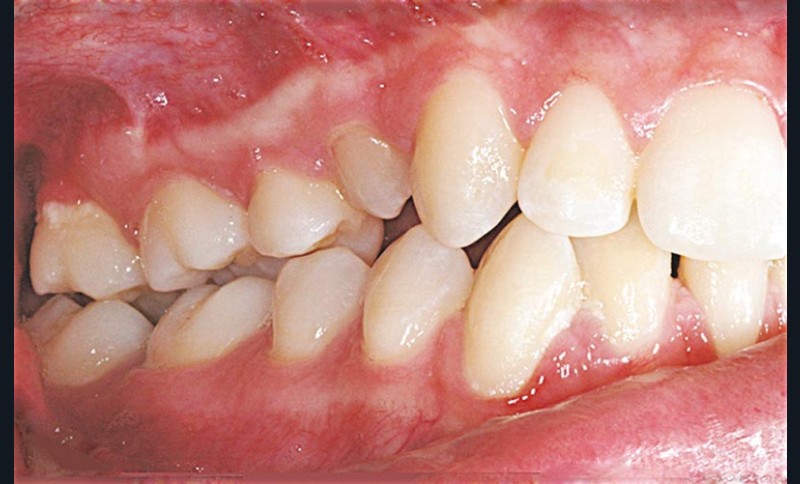

L’atteinte desmodontale, en particulier le risque d’ankylose, constitue un facteur limitant pour l’orthodontie. En effet, le déplacement orthodontique d’une dent dépourvue de desmodonte est tout simplement inconcevable sur le plan histologique ; sans compter les effets parasites engendrés au niveau des dents voisines (fig. 1).